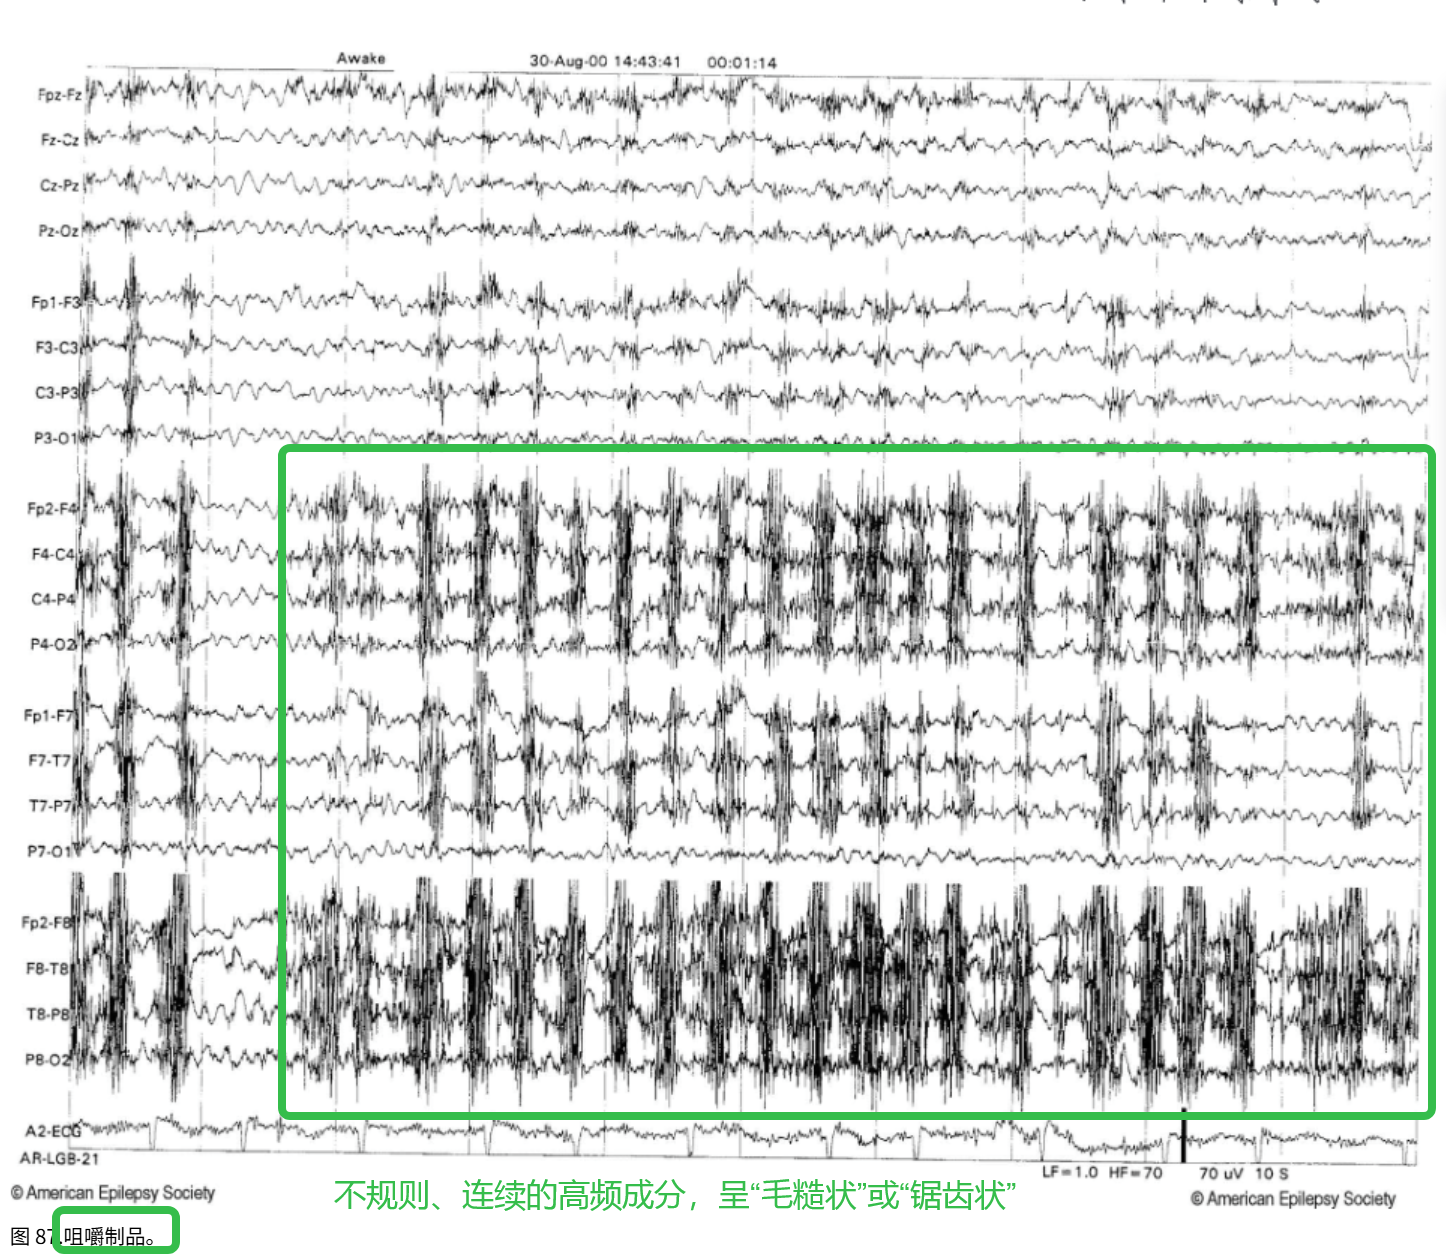

(4)肌电伪迹——咀嚼伪迹

区域:额区、颞区、下颌区

特征:不规则、连续,常呈“毛糙状”或“锯齿状”

波型:高频 β波

在这里插入图片描述